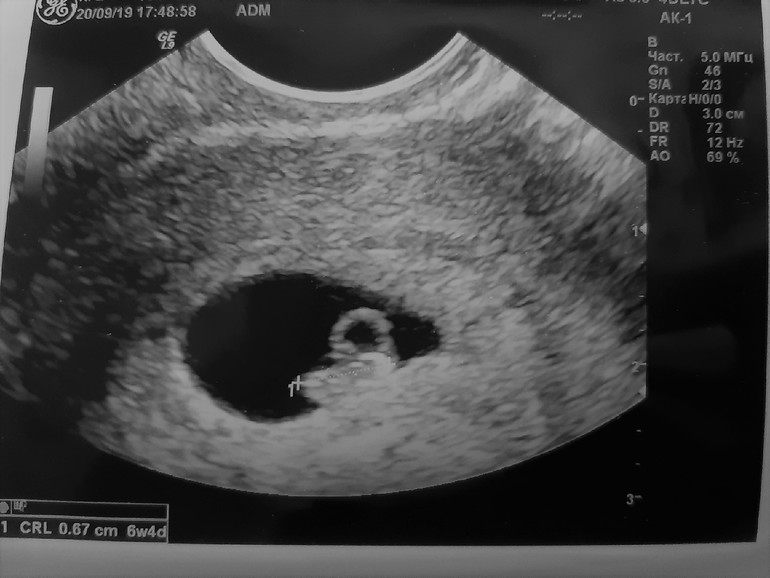

Вчера съездила на платное УЗИ.

Все хорошо, все мои опасения были напрасны, послушали сердечко и посмотрели на танцы вишенки))